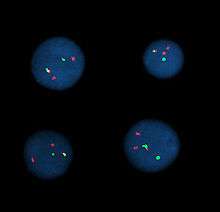

Interphase cells positive for a t(9;22) rearrangement

Fluorescent in situ hybridization (FISH) refers to using fluorescently labeled probe to hybridize to cytogenetic cell preparations.

Analysis

Analysis of FISH specimens is done by fluorescence microscopy by a clinical laboratory specialist in cytogenetics. For oncology generally a large number of interphase cells are scored in order to rule out low-level residual disease, generally between 200 and 1,000 cells are counted and scored. For congenital problems usually 20 metaphase cells are scored.